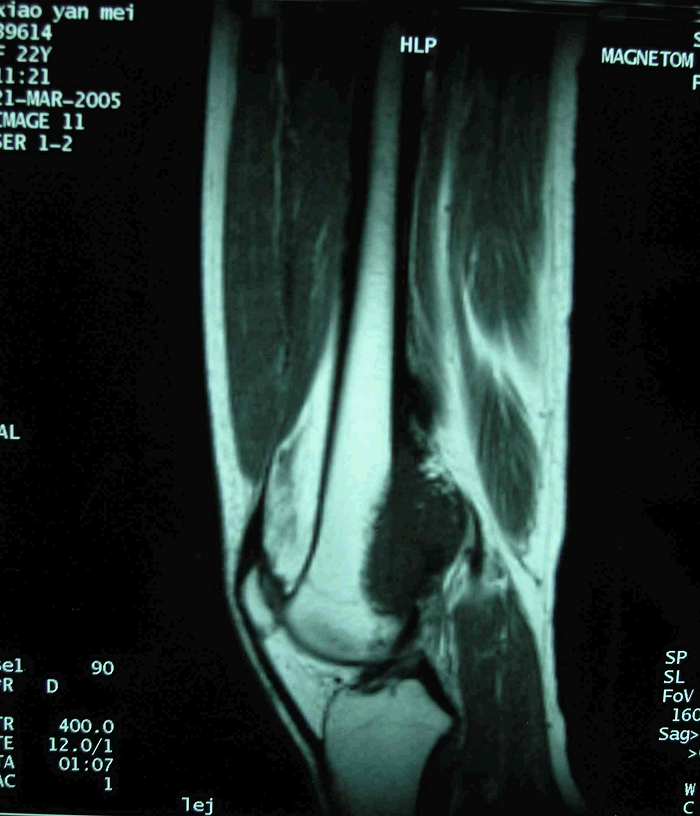

图 16术前MRI